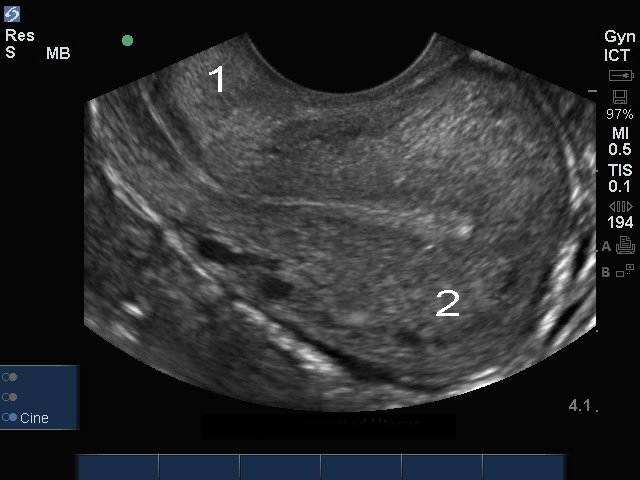

骨盤の経膣子宮: 子宮内膜画像

後傾子宮

頚部

眼底